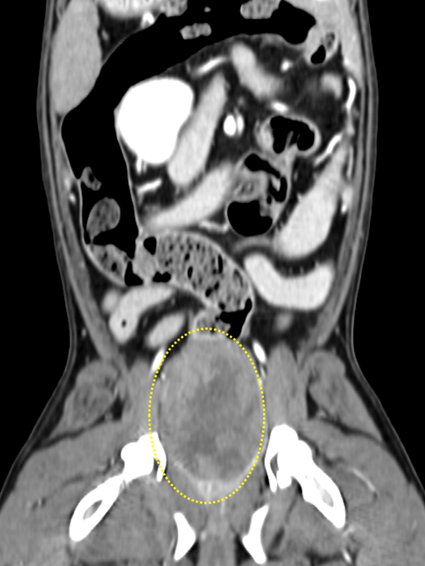

전산화단층촬영(CT)결과,

골반강 내 위치한 질의 원위부에

크기가 큰 타원형 종괴

(W 3.4cm * L 5.7cm * H 3.4cm)가 확인되었고,

질 근위부까지 이어져 내측으로 돌출되어

관찰되어 질 근육층 유래 종양이 의심되었습니다.

골반강 내에서 크게 확인되는 종괴

종괴로 인해 (노란타원) 압박받은 직장(화살표)직장.

- 내강이 거의 관찰되지 않을 정도로 압박되어 있어 배변에 어려움이 있었을 것으로 판단됨.